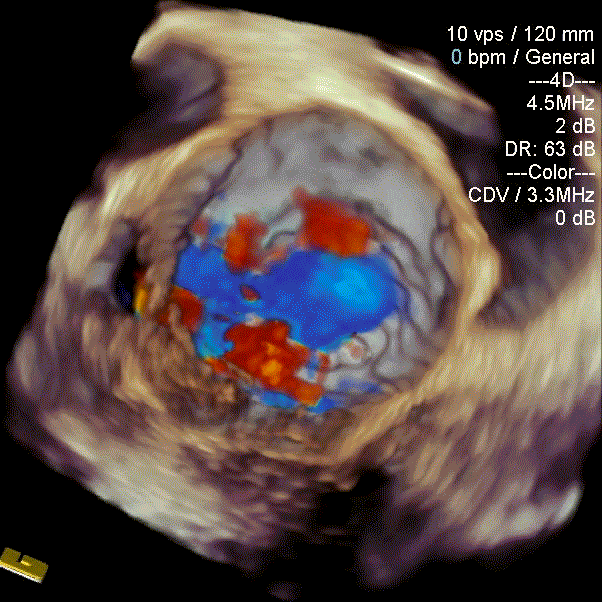

瓣中瓣植入后

无明显瓣中及瓣周反流